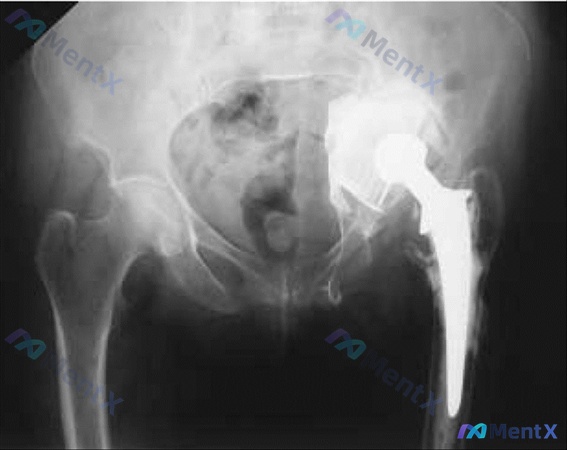

整理到一个有点挑战的关节置换术后病例,先放基础信息和影像描述,大家第一眼思路会怎么走? 基本情况 - 67岁女性 - 有类风湿关节炎病史 - 左全髋关节置换术后8年 本次表现 - 突发严重右侧颈部疼痛?不对,原文是右侧颈部疼痛但问题在臀部——重新确认:核心是腰部/臀部无法承受重量,否认额外疼痛或全身...